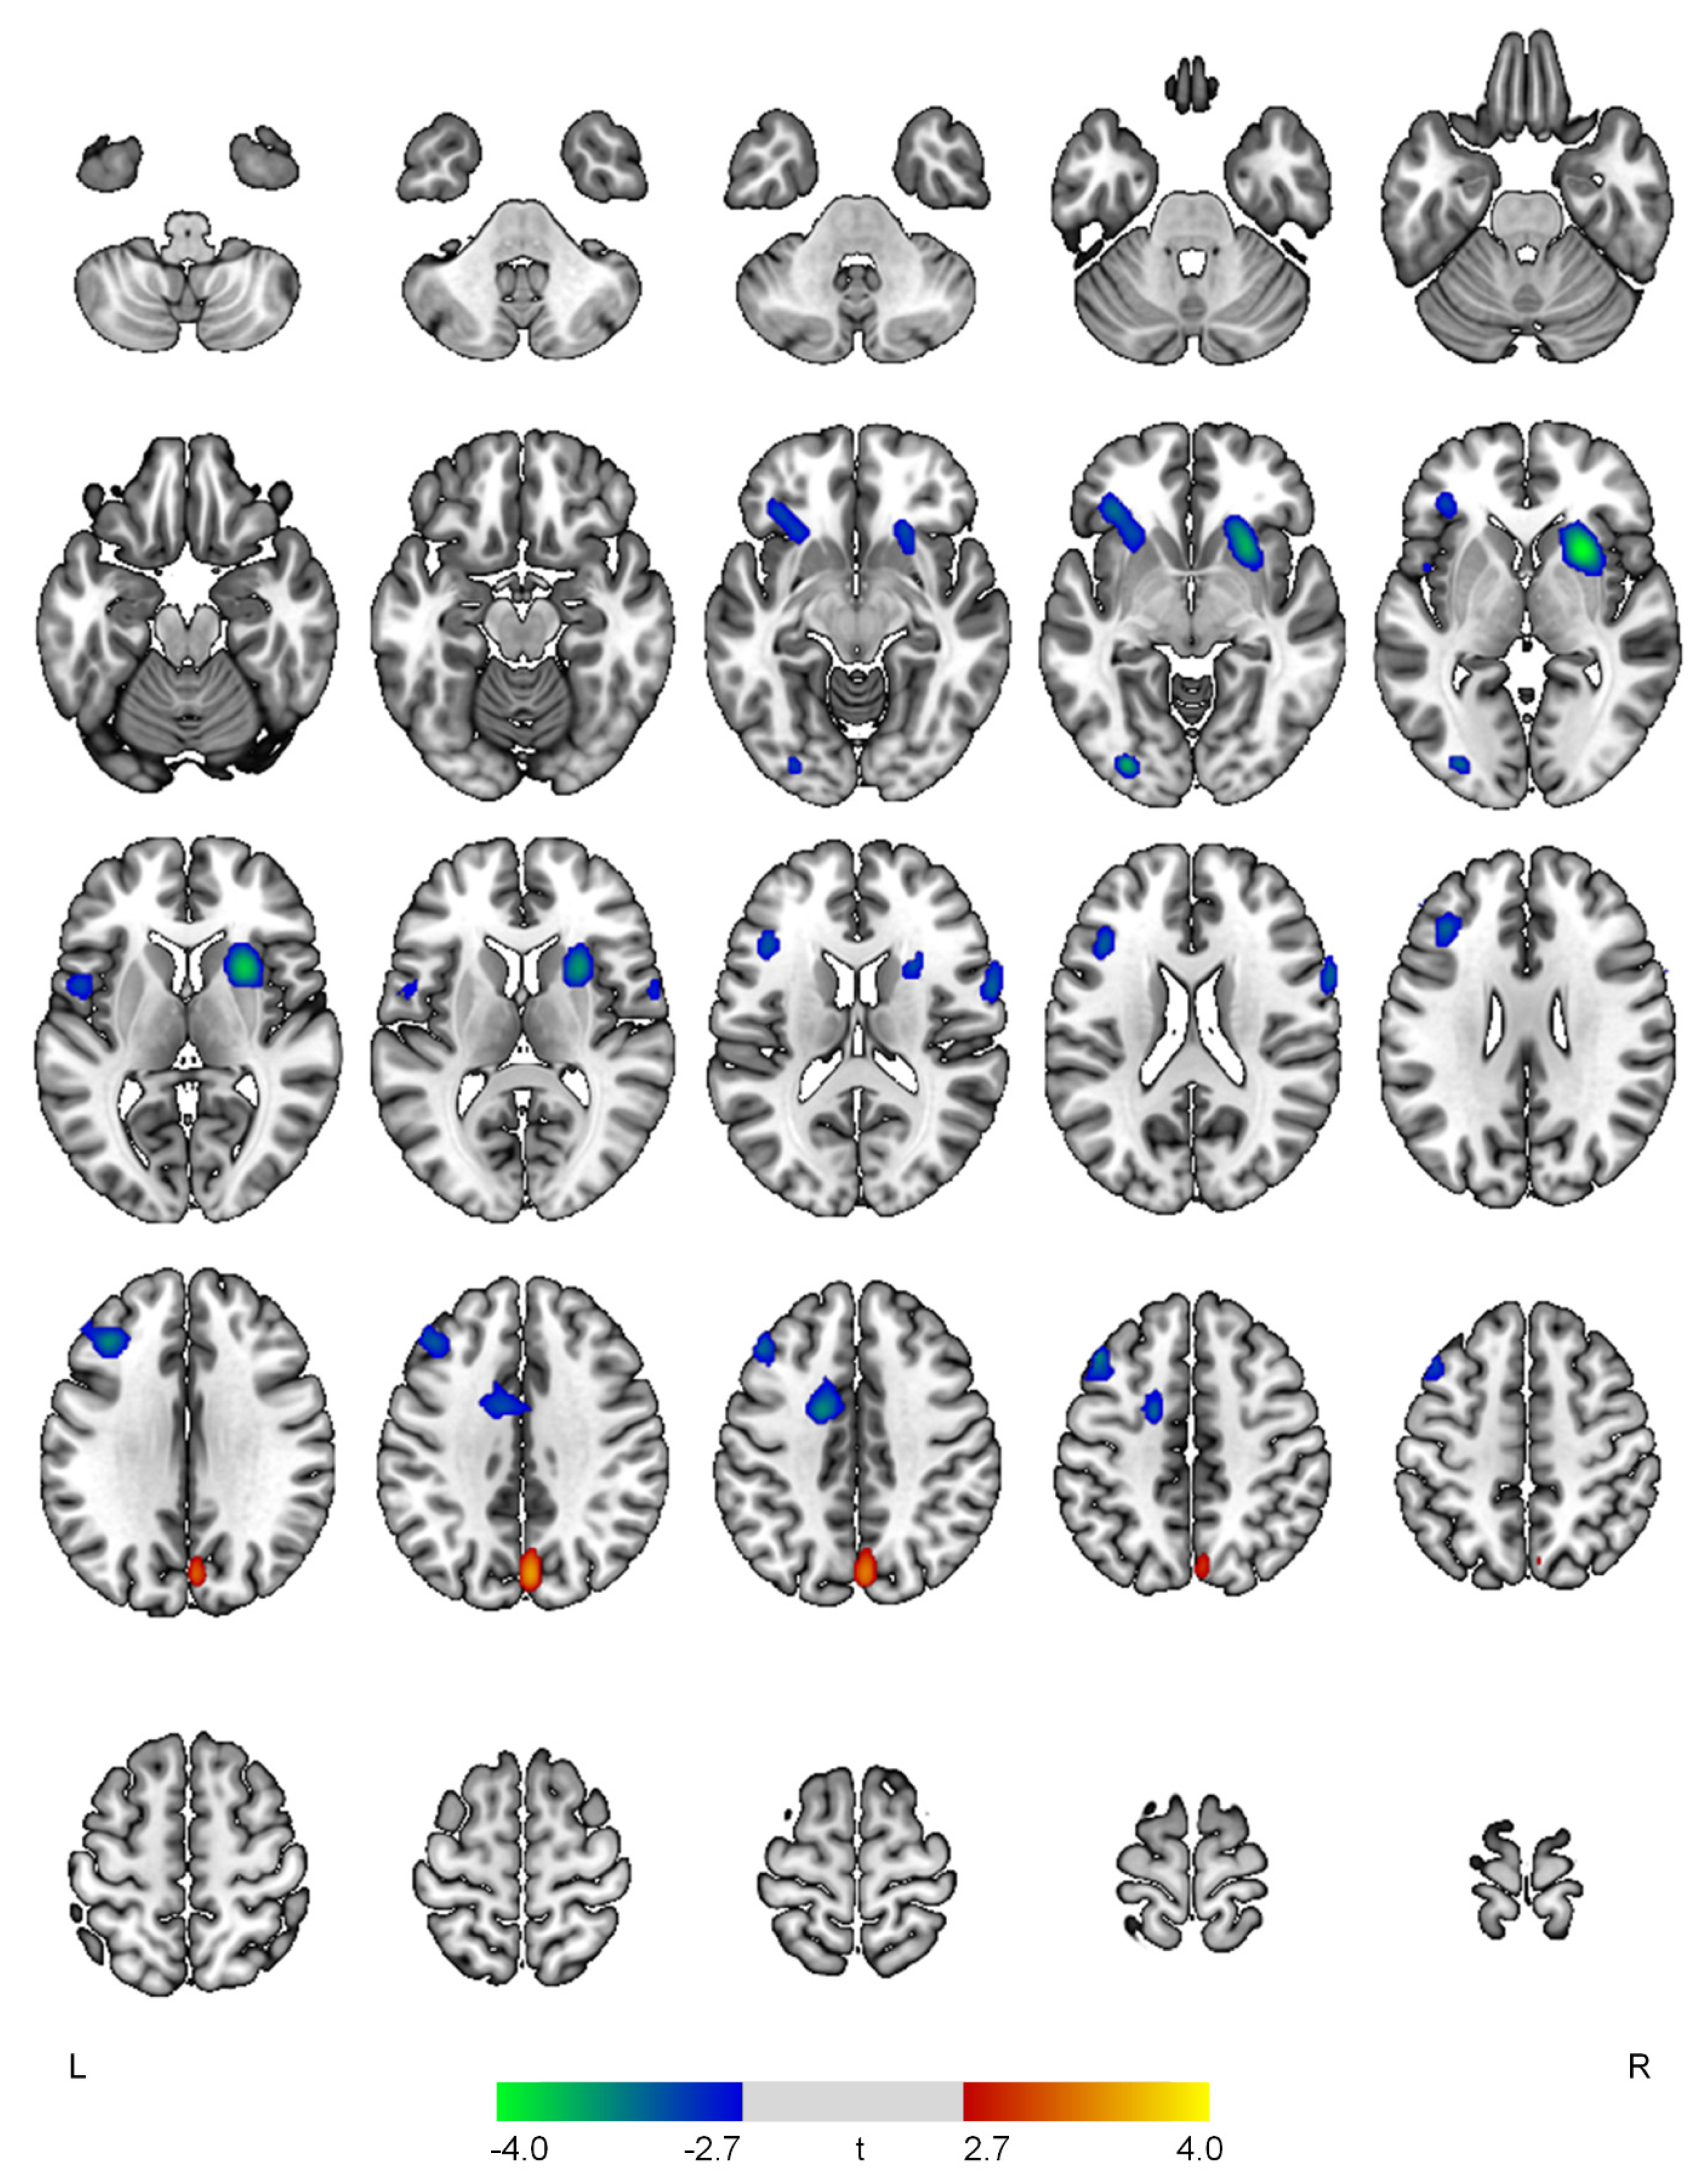

| Positive correlations with the psychosis domain | ||||

| R cuneus | 3.53 | <0.001 | 305 | 4, −76, 34 |

| Negative correlations with the psychosis domain | ||||

| R putamen | 4.06 | <0.001 | 921 | 26, 12, 0 |

| L inferior occipital gyrus | 3.64 | <0.001 | 131 | −30, −84, −4 |

| L middle frontal gyrus | 3.49 | 0.001 | 702 | −44, 24, 44 |

| L anterior cingulate gyrus | 3.46 | 0.001 | 350 | −14, 0, 42 |

| L inferior frontal gyrus | 3.30 | 0.001 | 368 | −34, 30, −6 |

| R precentral gyrus | 3.20 | 0.001 | 191 | 64, 10, 20 |

| L central operculum | 3.04 | 0.002 | 118 | −50, 4, 6 |